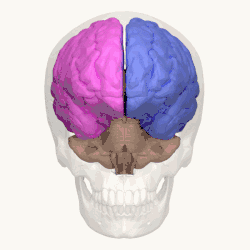

O cérebro humano é o órgão central do sistema nervoso humano e, com a medula espinhal, forma o sistema nervoso central. O encéfalo consiste no cérebro, no tronco cerebral e no cerebelo. O cérebro controla a maioria das atividades do corpo, ao mesmo tempo em que processa, integra e coordena as informações que recebe do sistema sensorial e toma decisões quanto às instruções enviadas ao resto do corpo. O órgão, que está contido e protegido pelos ossos do crânio da cabeça e é a maior parte do encéfalo humano, consiste em dois hemisférios cerebrais. Cada hemisfério possui um núcleo interno composto de matéria branca e uma superfície externa - o córtex cerebral - composto de matéria cinzenta. O córtex tem uma camada externa, o neocórtex e um alocórtex interno. O neocórtex é formado por seis camadas neuronais, enquanto o alocórtex tem três ou quatro. Cada hemisfério é convencionalmente dividido em quatro lobos cerebrais - frontal, temporal, parietal e occipital. O lobo frontal está associado às funções executivas, como autocontrole, planejamento, raciocínio e pensamento abstrato, enquanto o lobo occipital é dedicado à visão. Dentro de cada lobo, áreas corticais estão associadas a funções específicas, como as regiões sensoriais, motoras e de associação. Embora os hemisférios esquerdo e direito sejam bastante semelhantes em forma e função, algumas funções estão associadas especificamente a um lado, como a linguagem à esquerda e a habilidade visual-espacial à direita. Os hemisférios são conectados por tratos nervosos comissurais, sendo o maior o corpo caloso.

Hemisférios

O hemisfério dominante em 98% dos humanos é o hemisfério esquerdo, é responsável pelo pensamento lógico e competência comunicativa. Enquanto o hemisfério direito, é responsável pelo pensamento simbólico e criatividade, embora pesquisas recentes estejam contradizendo isso, comprovando que existem partes do hemisfério direito destinados a criatividade e vice-versa. Nos canhotos as funções estão invertidas. O hemisfério esquerdo diz-se dominante, pois nele localiza-se 2 áreas especializadas: a Área de Broca (B), o córtex responsável pela motricidade da fala, e a Área de Wernicke (W), o córtex responsável pela compreensão verbal.

O corpo caloso, localiza-se no fundo da fissura inter-hemisférica, ou fissura sagital, é a estrutura responsável pela conexão entre os dois hemisférios cerebrais. Essa estrutura, composta por fibras nervosas de cor branca (freixes de axónios envolvidos em mielina), é responsável pela troca de informações entre as diversas áreas do córtex cerebral.